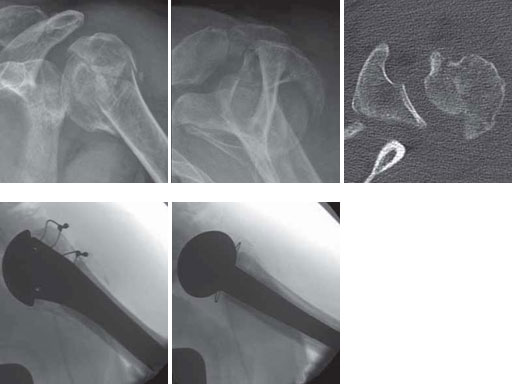

61-year-old male with a 4-part-fracture of the humeral head (head-splitting fracture).

Case provided by Norbert P Sdkamp, Martin Jaeger, Freiburg, DE, Ralph Hertel, Bern, CH

Fig 3ac Fracture situation in conventional x-rays and CT scan.

Fig 3de Implantation of a fracture prosthesis type EPOCA.